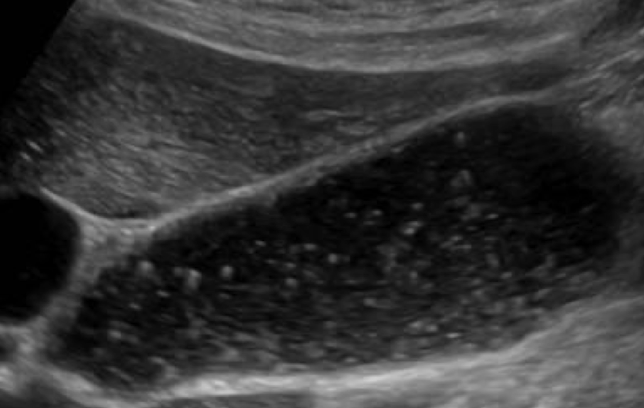

sludge ball

aka tumefactive sludge

clumping of sludge

larger than gallstone

mobile; no shadowing